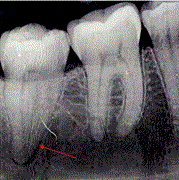

Burkitt’s lymphoma: an unexpected cause of dental pain

William D Parker and Keith Jones

Journal of Surgical Case Reports, Volume 2021, Issue 2, February 2021, rjaa557, https://doi.org/10.1093/jscr/rjaa557